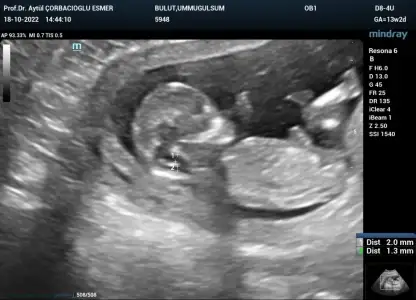

Selamlarrr, kontrolden çıktık, ikili test verdik. Ultrason detaylı bakıldı sağlıklı şimdilik kan verdik ama hâlâ cinsiyet net değil :110:

• 300DB844-D67B-4FD8-A8EC-C6CF955484D3.webp

300DB844-D67B-4FD8-A8EC-C6CF955484D3.webp

37 KB · Görüntüleme: 83